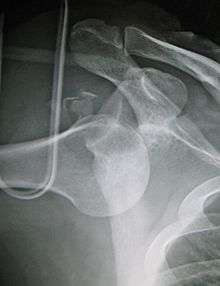

- An anterior dislocation of the shoulder

Anterior dislocation of the right shoulder. AP X ray

Anterior dislocation of the right shoulder. Y view X ray.

Inferior dislocation is the least likely, occurring in less than 1%. This condition is also called luxatio erecta because the arm appears to be permanently held upward or behind the head.[8] It is caused by a hyper abduction of the arm that forces the humeral head against the acromion. Such injuries have a high complication rate as many vascular, neurological, tendon, and ligament injuries are likely to occur from this mechanism of injury.